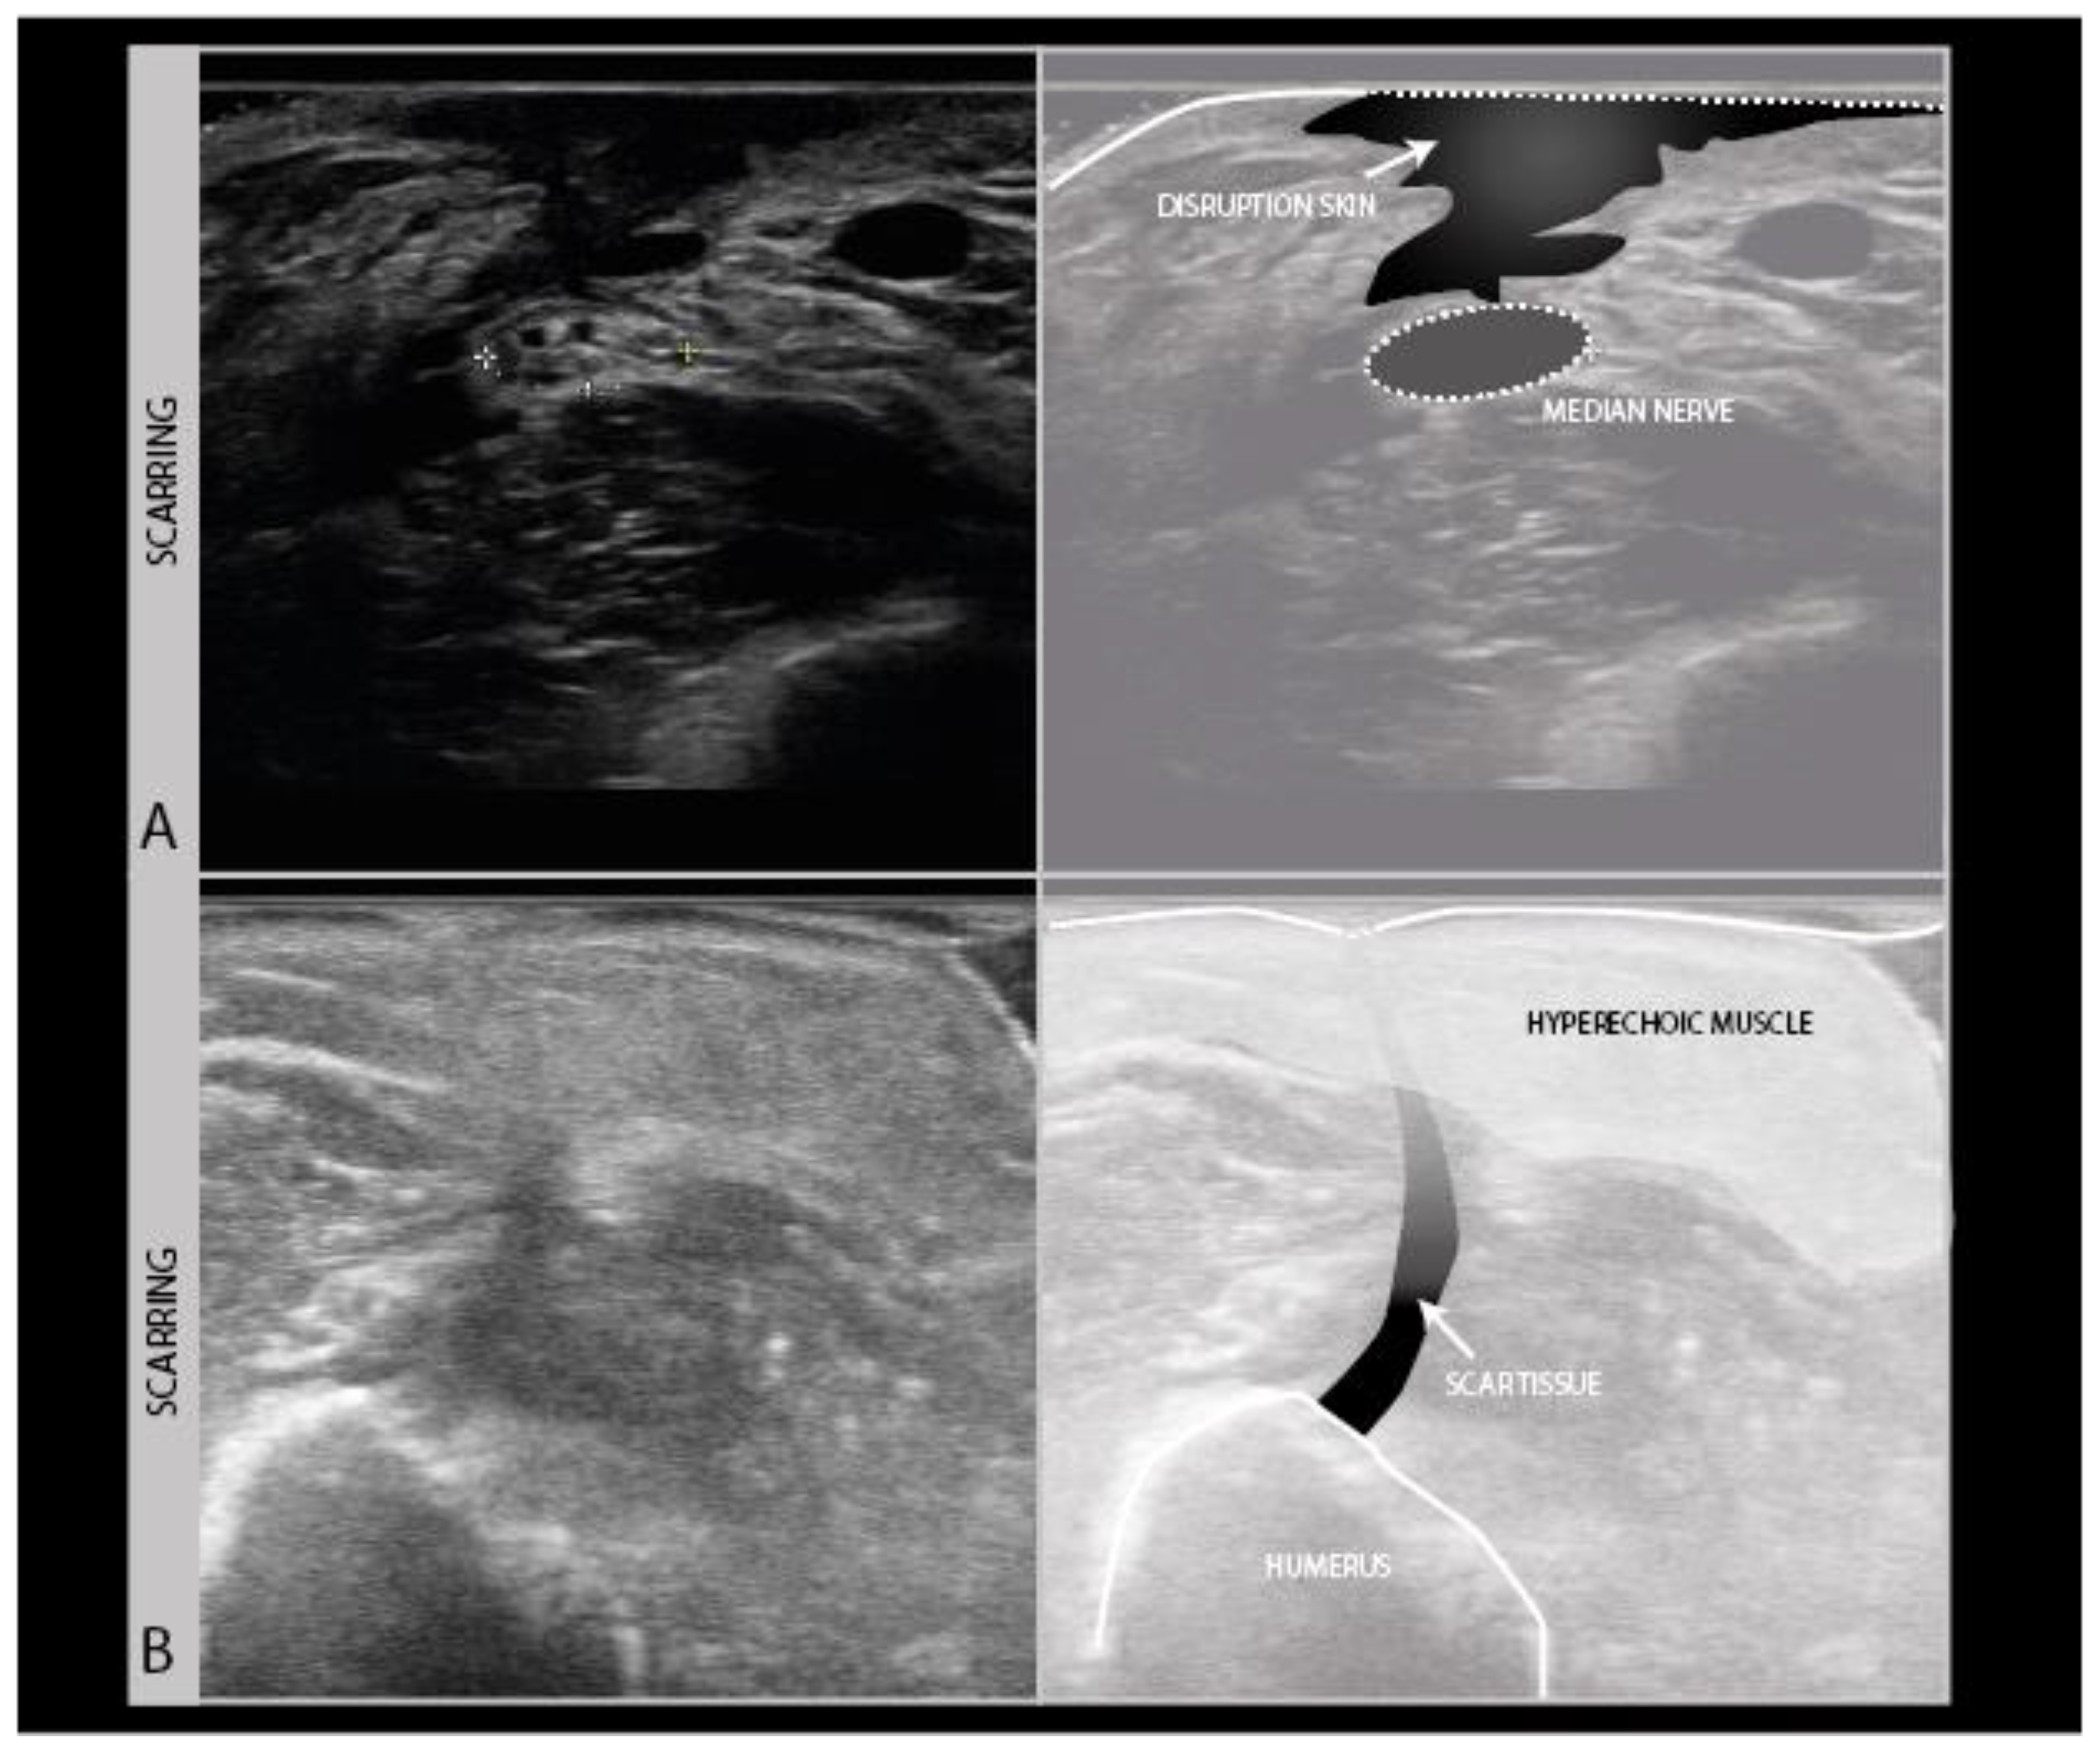

During the ultrasound scanning of nerve trauma patients, it is not only important to look at the nerve itself, but also to scan its anatomical surroundings for any abnormality that may impact on nerve recovery or pose an additional problem for the patient. The most commonly observed abnormality in trauma is scarring. As scars often run perpendicular to the skin surface, they are hard to visualize well with ultrasound, as the soundwaves travel parallel to the lines of the scar and almost nothing gets reflected back to the probe. Scars therefore show up as vaguely defined hypoechogenic longitudinal lines in the skin, subcutaneous tissue and fascia (Figure 8A), sometimes only visible by the interruption of other architectural features in those layers (Figure 8B).

Figure 8.

Examples of scarring of the skin and subcutis. Severe disruption of skin and subcutaneous tissue showing as a craggy hypoechogenic region over a median nerve neuroma in continuity in a patient with the piercing trauma of the forearm by a wooden fence (A). Hyperechogenic subcutis and muscle following surgery for an open humerus fracture, with a subtle vertical scar line interrupting the tissue layers (B).

Scarring can also involve the nerve and its connective tissue ensheathing itself (Figure 9A), and can lead to a loss of nerve elasticity and adhesions to surrounding tissues (Figure 9B).